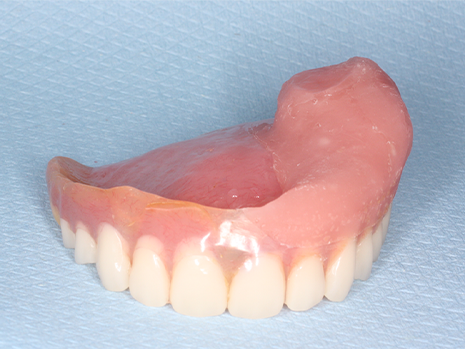

restore function and appearance after surgical resection.

implants, grafts, or maxillofacial prosthetics to restore chewing, speech, and facial contours.